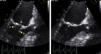

O Eco transesofágico, exame mal tolerado pelo doente causando taquicardia sinusal (FC 115bpm), confirmou a presença de folhetos valvulares com razoável abertura mas mostrou estrutura hiperecogénica aposta à face auricular do anel mitral, distal à inserção do apêndice auricular esquerdo (Figura 3), gerando gradiente diastólico AE/VE médio muito elevado (39mmHg). A área do orifício efetivo, estimada pelo método de PISA, foi de 0,7cm2, reforçando a hipótese de anel mitral (Figura 4). Não foram identificadas outras anomalias congénitas.

Ecocardiograma transesofágico (plano 121°): morfologia da válvula mitral em diástole (à esquerda) e em sístole (à direita); observam‐se os folhetos posterior (seta A) e anterior (seta B) com boa abertura e destaca‐se a presença de uma estrutura ecogénica a nível da face auricular do anel mitral (seta verde).

Ecocardiograma transesofágico (plano 121°): à esquerda, destaca‐se pequena zona de isoconvergência (mal visualizada em ecocardiograma transtorácico) a sugerir estenose a nível do anel mitral; a área de orifício efetivo estimada pelo método de PISA foi de 0,7cm2; à direita, gradiente transmitral máximo de 54mmHg e médio de 39mmHg.